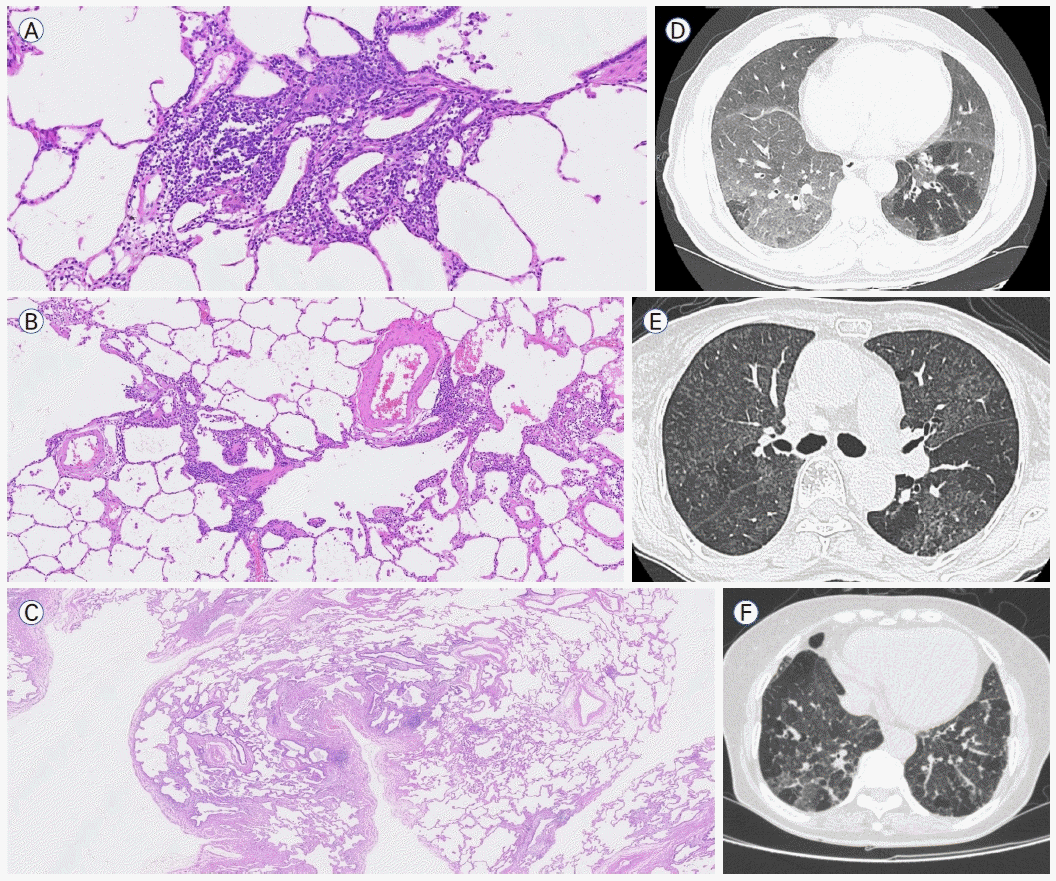

BIP는 간질의 염증과 섬유화가 혼재되어 있을 수 있다(Fig. 2A-C). 비섬유성(또는 세포성) BIP의 병리학적 특징은 세기관지를 둘러싸는 림프구-우세 만성 염증 소견이며 비괴사성 육아종이 동반될 수 있다. 섬유성 BIP는 세기관지 중심의 섬유화를 특징으로 하며 인접한 폐포에서는 세기관지 주위 화생(peribronchiolar metaplasia)이 종종 관찰된다. 비섬유성 BIP의 전형적인 CT 소견은 세기관지 주위 염증을 시사하는 중심소엽성 결절과 소기도 폐쇄를 시사하는 모자이크 음영 및 공기 저류이다(Fig. 2D, E). 섬유성 BIP에서는 간유리음영, 망상 음영, 견인기관지 확장, 삼상 폐밀도 양상, 호기시 공기 저류의 소견이 기관지혈관 주위 분포를 보인다(Fig. 2F) [9]. 이러한 소견들은 임상적 상황이 맞다면 HP를 강력하게 시사하는 소견들이지만 CTD-ILD 등 다른 원인에 의한 간질성 폐렴에서도 관찰될 수 있다[10].

Figure 2.

Pathologic (haematoxylin and eosin stain) and radiologic features of the BIP pattern. Histological pattern of non-fibrotic BIP (A) with lymphocyte-predominant inflammatory cell infiltration with poorly formed nonnecrotizing granuloma (× 200) and (B) bronchiolocentric cellular infiltration (× 100). Lung biopsy of fibrotic BIP (C) showing centrilobular interstitial fibrosis (× 20). Mild cellular infiltration and peribronchiolar metaplasia are accompanied. Axial CT of non-fibrotic BIP (D) showing bilateral groundglass opacities and air-traping and (E) diffuse bilateral poorly defined centrilobular nodules with ground-glass opacity interposed with patchy areas of decreased attenuation. Axial CT of fibrotic BIP (F) shows heterogeneous bilateral ground-glass opacity with minimal superimposed reticulation, lobular areas of decreased attenuation and the three different densities [28]. BIP, bronchiolocentric interstitial pneumonia; CT, computed tomography.